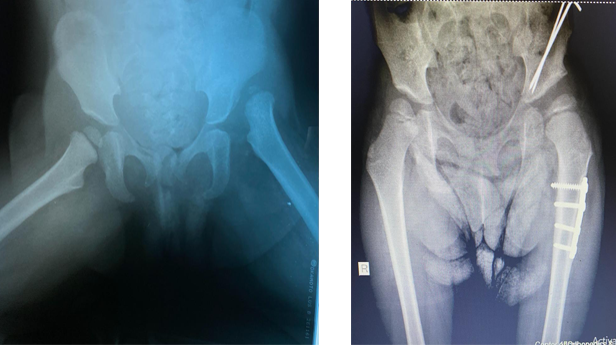

Hip dysplasia in children and adolescents

If a baby is born in a breech position, a pediatrician can detect or diagnose hip dysplasia with ultrasound. Our team treats children with this disorder by non-surgical means, in addition to surgical procedures if necessary.